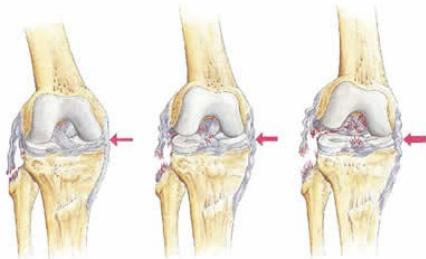

Collateral Ligament Injuries

Medial Collateral Ligament (MCL) Injury

Mechanism:

- Valgus stress to the knee

- Most commonly occurs at medial femoral attachment

Lateral Collateral Ligament (LCL) Injury

Characteristics:

- Isolated LCL injuries are uncommon